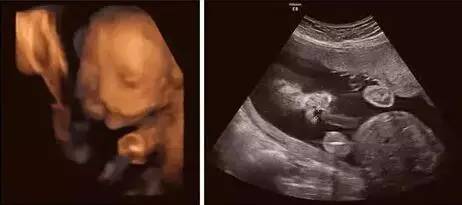

超声影像(四维彩超),帮你排除宝宝先天缺陷

四维查出胎儿唇裂,为所有孕妈敲响警钟!

双胎宝妈21周做四维彩超,筛查出一名胎儿为"唇腭裂"

想知道宝宝是否健康 超声影像(四维彩超) 针对22—28周之间的宝妈

b超排畸:洛阳牡丹妇产医院ge-e10高清四维彩超可多方位,多角度地观察